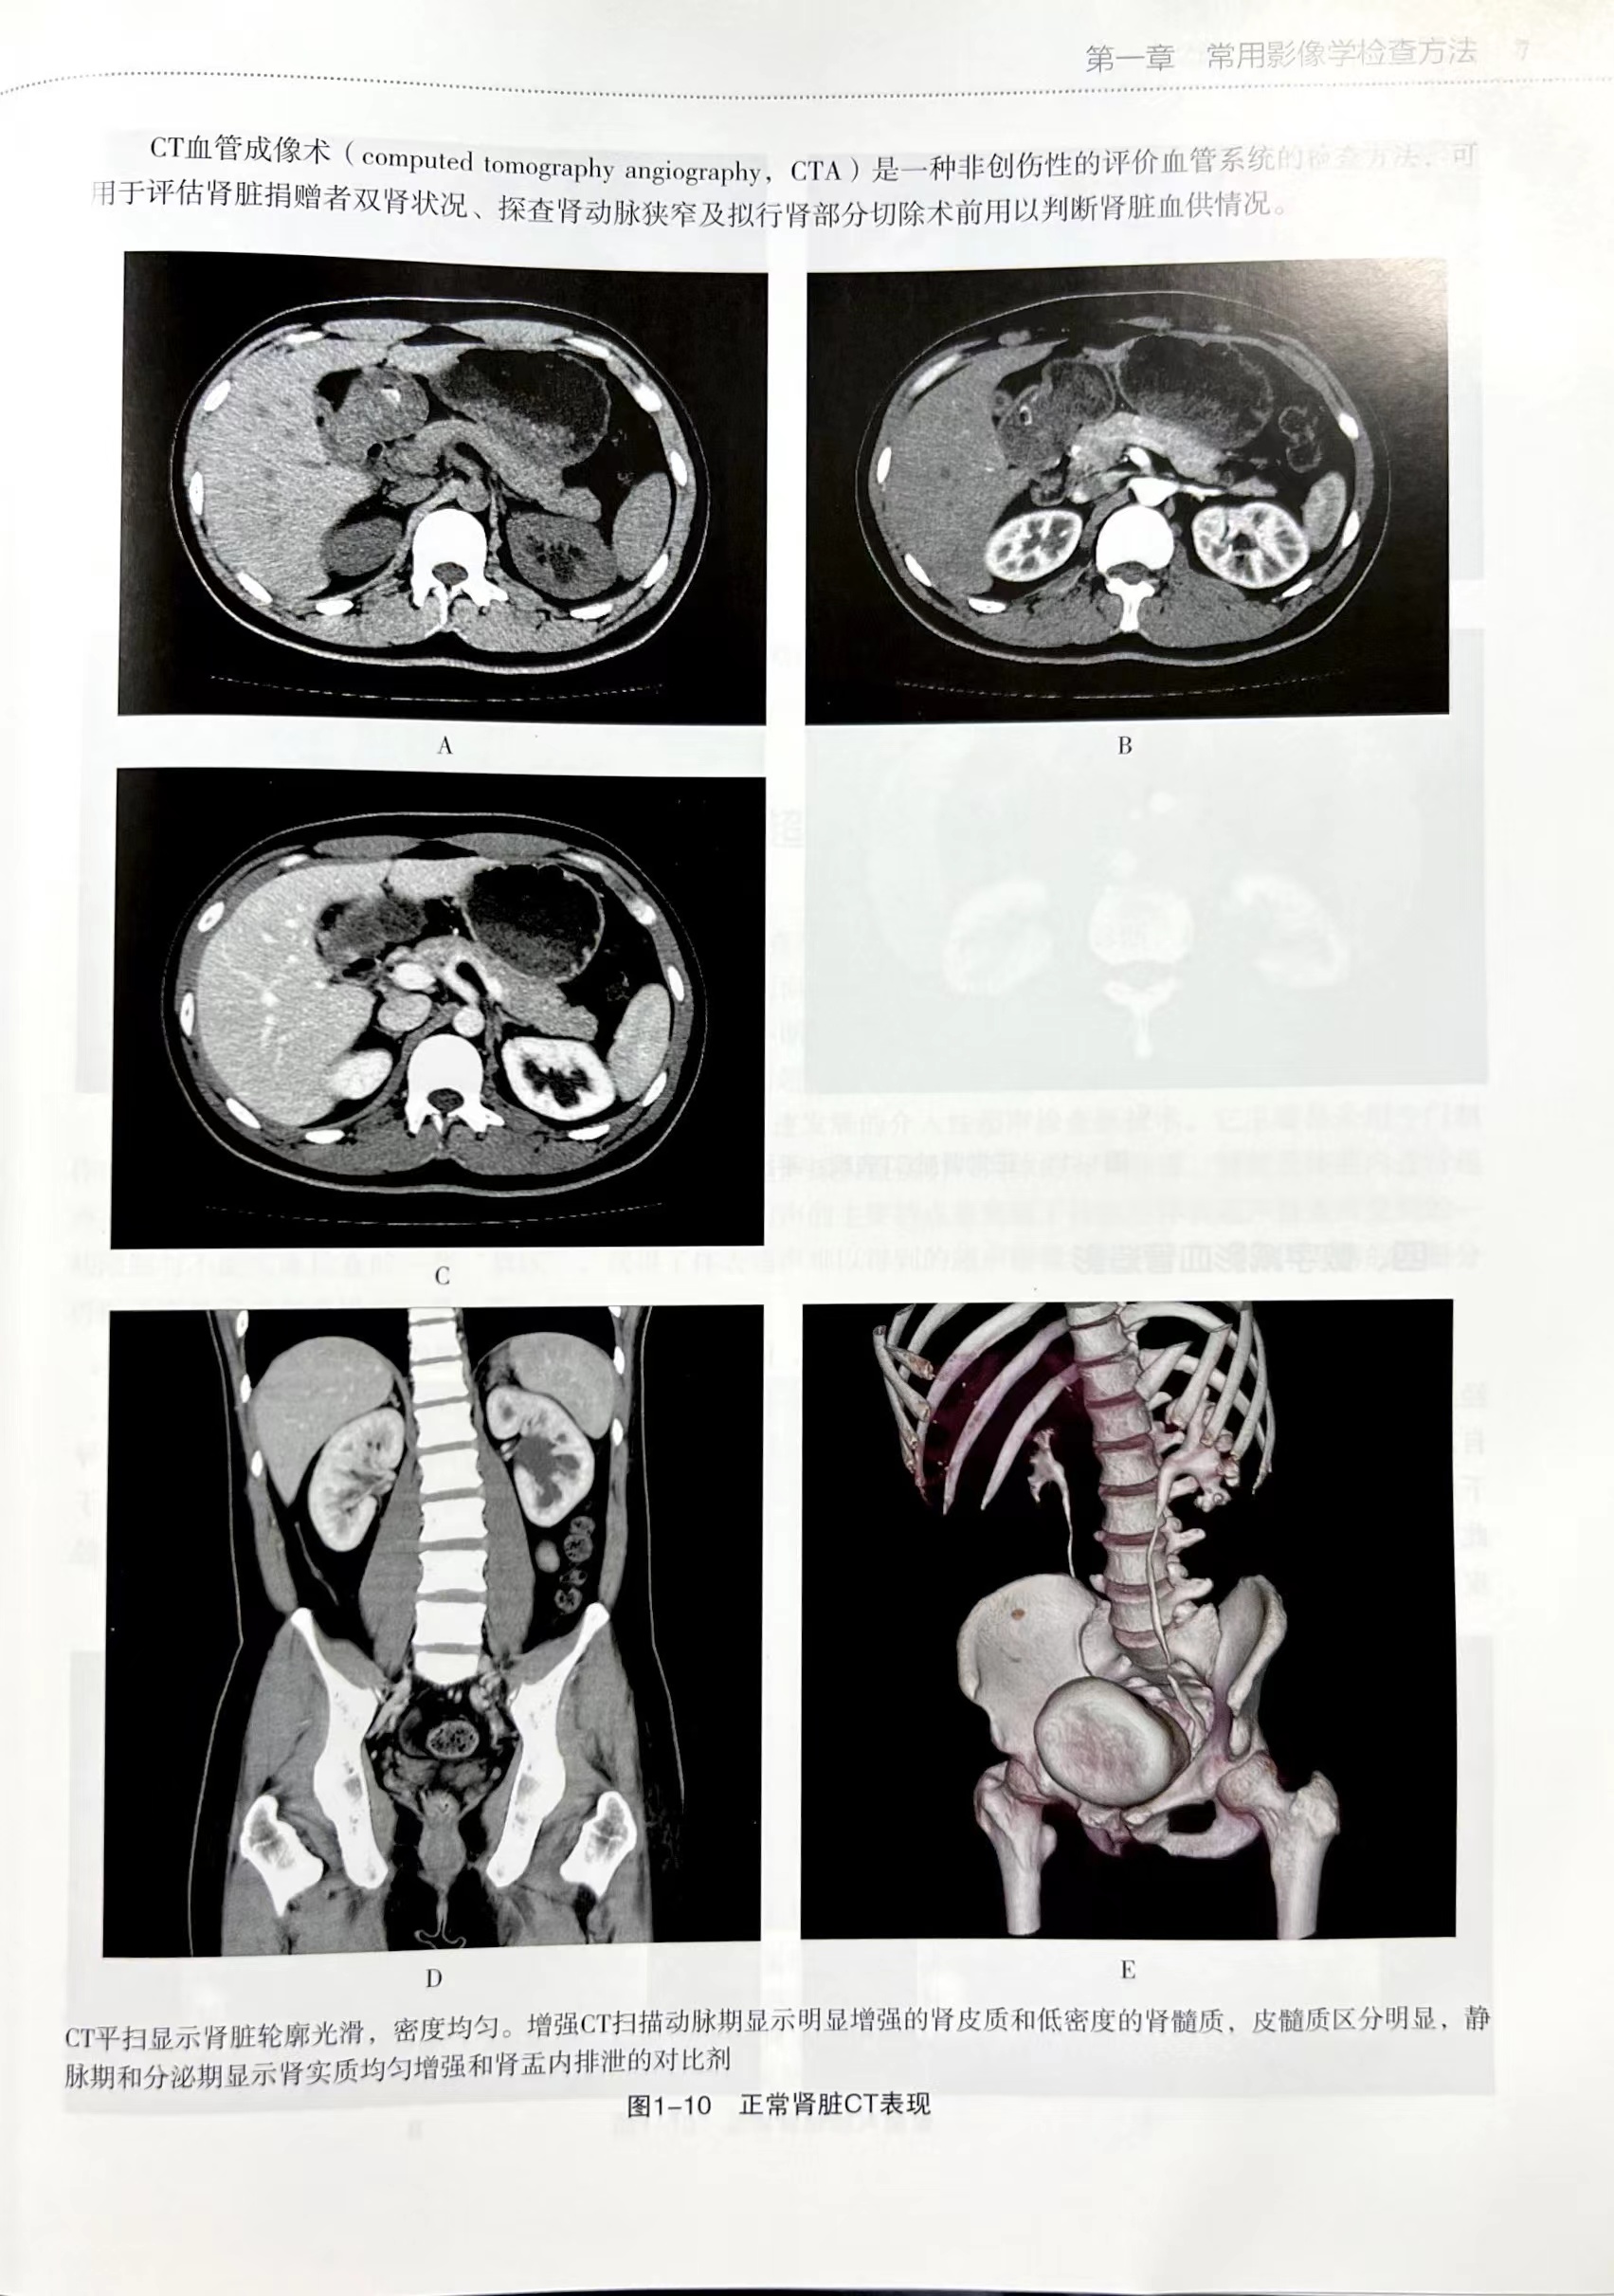

本书共分为九章。第一章先介绍了泌尿外科常用影像学检查方法。第二章到第九章按照泌尿外科涉及的器官进行分类叙述,并且按照解剖位置从上到下进行,包括肾上腺、肾脏、输尿管、膀胱、前列腺与精囊、尿道、阴囊内容物及输精管、阴茎共八大器官组织。每一章节先简单描述其正常解剖与毗邻结构,然后叙述该器官常见的疾病。每种疾病均先简单概括其临床特点,然后描述其影像学表现,包括B超、X线、CT、MRI等,部分病例还展示了手术标本,并追踪术后病理结果,力求将每个疾病的临床特点、影像学征象、病理结果对应起来。对部分罕见的病例,我们临床工作中未遇到的典型影像照片,通过搜寻国内外文献并将相关图片在本书中呈献给读者。